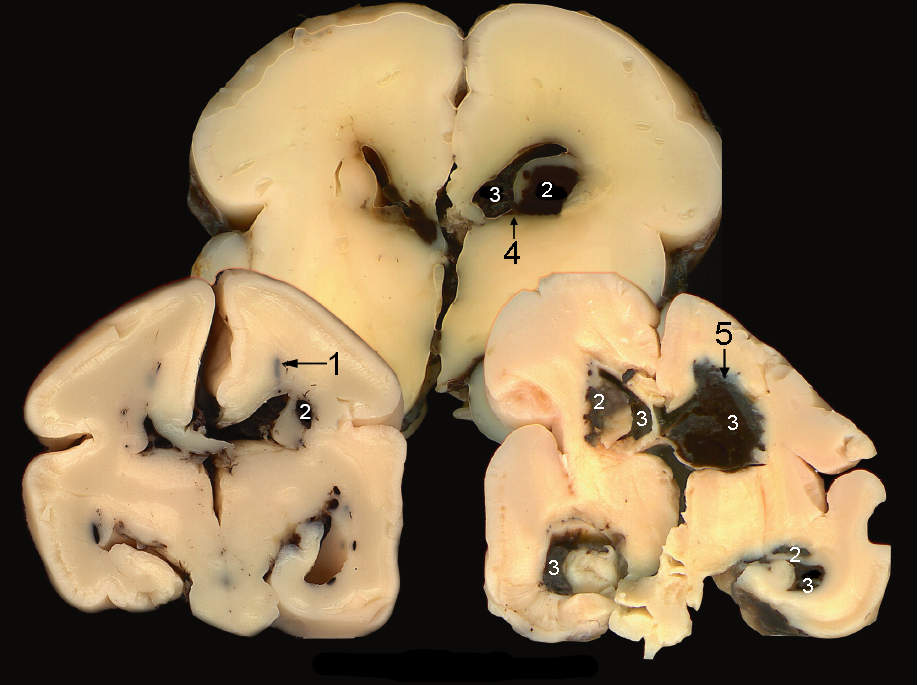

Neonatology GMH IVH Brain Dissection Graphic

1.  Distended Vein

2.  Germinal Matrix Hemorrhage (GMH)

3.  Intraventricular Hemorrhage (IVH)

4.  Dissection to Stria Terminalis: Intraventricular Hemorrhage (IVH)

5.  Venous Infarction